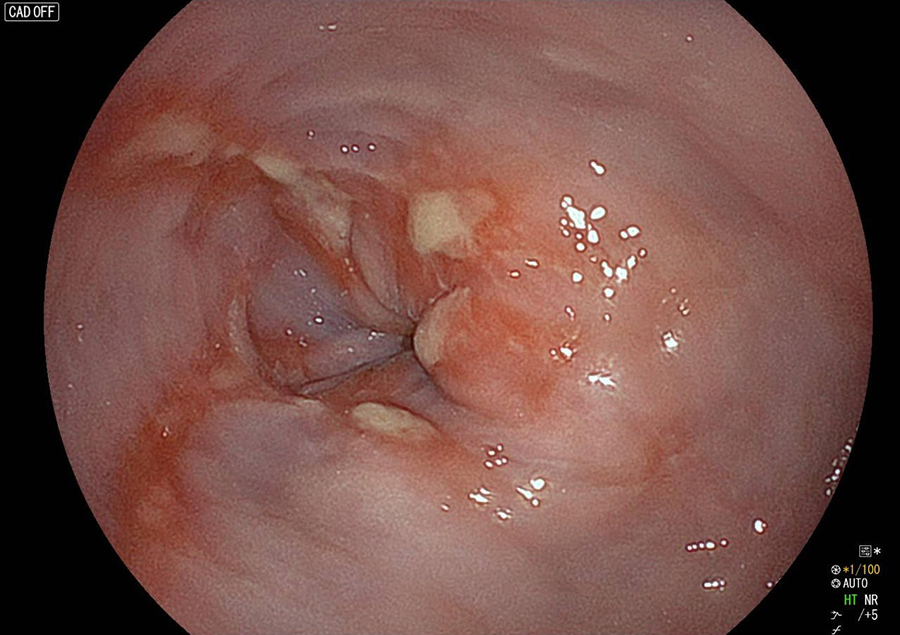

胃カメラ検査では、口又は鼻から内視鏡を挿入し、食道・胃・十二指腸の一部を観察します。直接胃や食道の粘膜を観察することができるので、色調や微妙な凹凸の変化が分かり、潰瘍・炎症・ポリープ・腫瘍などの診断が可能です。

胃カメラでわかる病気/病変

検査の様子